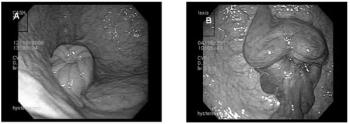

Endoscopic examination in the stallions is indicated in cases where blood (hemospermia), pus or (pyspermia) in the semen or urine, treatment for seminal vesiculitis, pain on ejaculation, or there is an inability to emit semen.

Endoscopic examination of the mare's uterus is primarily used as tool to aid in the diagnosis of unusual conditions, such as intractable infections, tumors, abscesses, foreign bodies, adhesions, and congenital abnormalities.